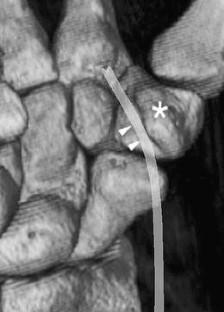

Five of the patients showed evidence of triscaphe osteoarthritis. One of the patients showed synovitis and reactive marrow edema at the triscaphe joint without more specific findings of osteoarthritis. Five patients showed evidence of FCR tenosynovitis. Partial-thickness tears were noted in three patients. Two patients showed complete discontinuity of the FCR; one of them had undergone prior tendon harvesting for interposition arthroplasty after trapezectomy. One patient showed a ganglion cyst in connection to the FCR tendon sheath.

The FCR tendon courses over the volar surfaces of the scaphoid and trapezium in a separate fibro-osseous tunnel. This anatomical and functional relationship explains the coexistence of FCR tendinopathy and STT arthritis demonstrated by MR imaging.